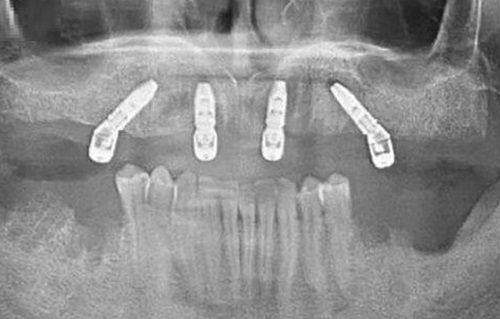

益阳伢贝健口腔引进了精良的种植技术,如美国3i种植系统。该系统具有精细度高、稳定性强的特点,能够大大提高种植牙的成功几率。同时,医院还采用了数字化导板种植技术,通过严谨的术前规划,让种植过程更加安心、效率高。

益阳华雅口腔配备了名列前茅的口腔诊疗设备,如3D口腔扫描仪、激光治疗仪等。这些设备能够为医生提供更正确的诊断信息,从而制定出更科学的治疗方案。3D口腔扫描仪可以快速、正确地获取患者口腔的三维数据,为种植牙手术提供严谨的指导。

2.种植系统多样

医院引进了多种国内外有名的种植系统,如瑞士士卓曼种植系统、瑞典诺贝尔种植系统等。不同的种植系统具有不同的特点和优势,医生会根据患者的具体情况为患者推荐更适合的种植系统。这样可以满足不同患者的需求,提高种植牙的成功几率和舒适度。